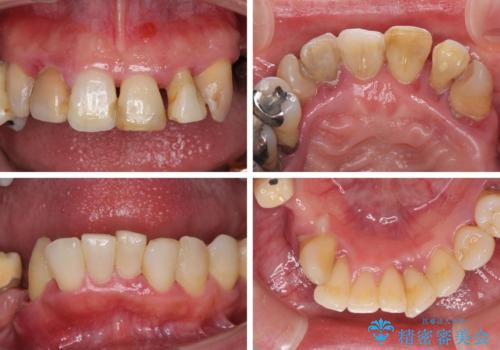

- 歯周病を放置したことで奥歯が抜け、前歯も痛くなってきたとのことで来院された患者様です。

奥歯はほとんどを抜歯しなければならない状態であり、抜歯をせずに済む歯も歯周外科処置や矯正治療を行う必要がある状態でした。

歯を抜かないといけない部分はインプラントとオールセラミッククラウンにより咬合を回復させ、歯周外科処置を行う歯については、同じくオールセラミッククラウンにて補綴治療を行うこととしました。

外科処置を多く行ったため、その待ち時間が長くかかり、さらには途中矯正治療も行なったので、治療期間は長期間となりました。